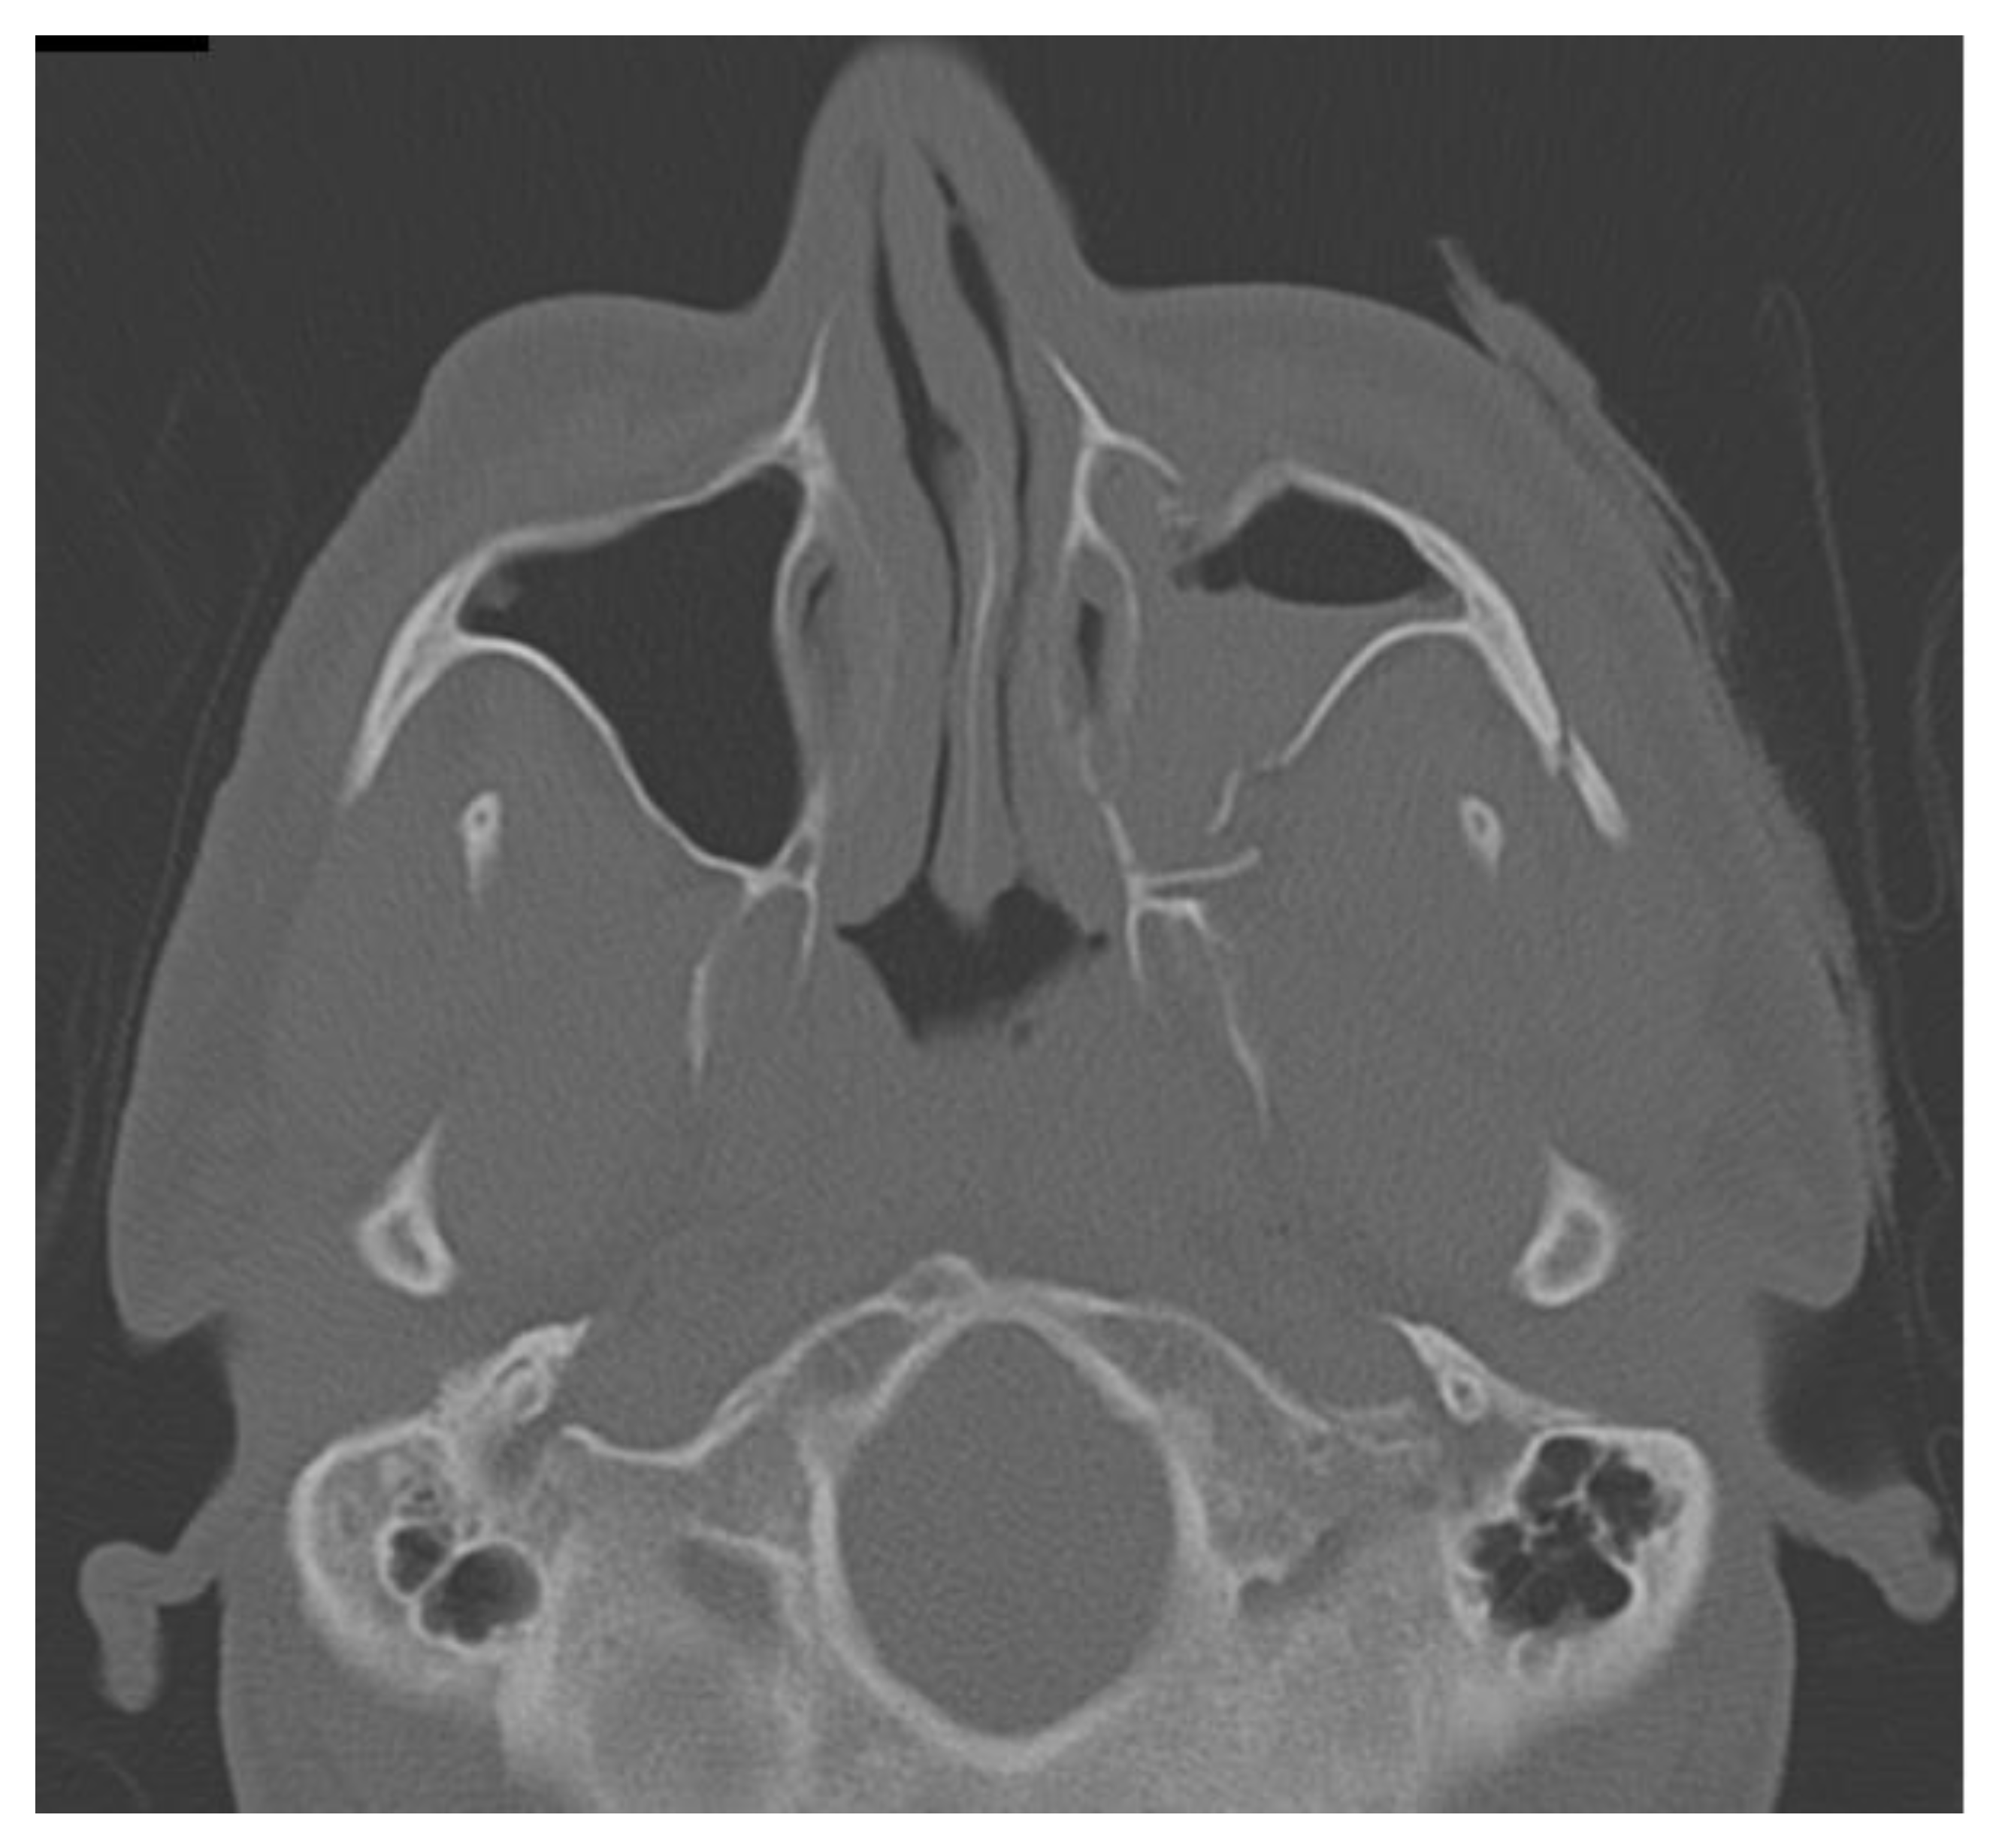

A 36 year-old male suffered from a blunt craniofacial trauma on the left temporal region caused by a baseball bat beating. The patient was admitted to the emergency department and then to the Ward of Maxillo-Facial Surgery. Because of the excessive fractures of the temporal bone along with the skull base and middle cranial fossa, the patient required intense monitoring (Figure 1, Figure 2, Figure 3, Figure 4, Figure 5 and Figure 6). Neurological status was fine; no CSF leak was present. No neurosurgical intervention to lift the displaced bone was used because of the close proximity of the meningeal artery in the fractured temporal bone region, which might cause serious, life-threatening bleeding. Secondly, the displacement was slightly less than 5 mm in total and symptomless. Detailed trauma-CT scans and 3D visualization revealed a fracture of the cranial base, along with the middle cranial fossa vault, cranial displacement of some part of the left frontal bone, and a fracture of the left zygomatic-orbital complex (Figure 7, Figure 8, Figure 9 and Figure 10).

Figure 8. Trauma CT in axial view with visible orbital, zygomatico-malar fractures and displaced zygomatic arch.

Figure 9. Trauma CT in an axial scan with visible temporal bone fractures.